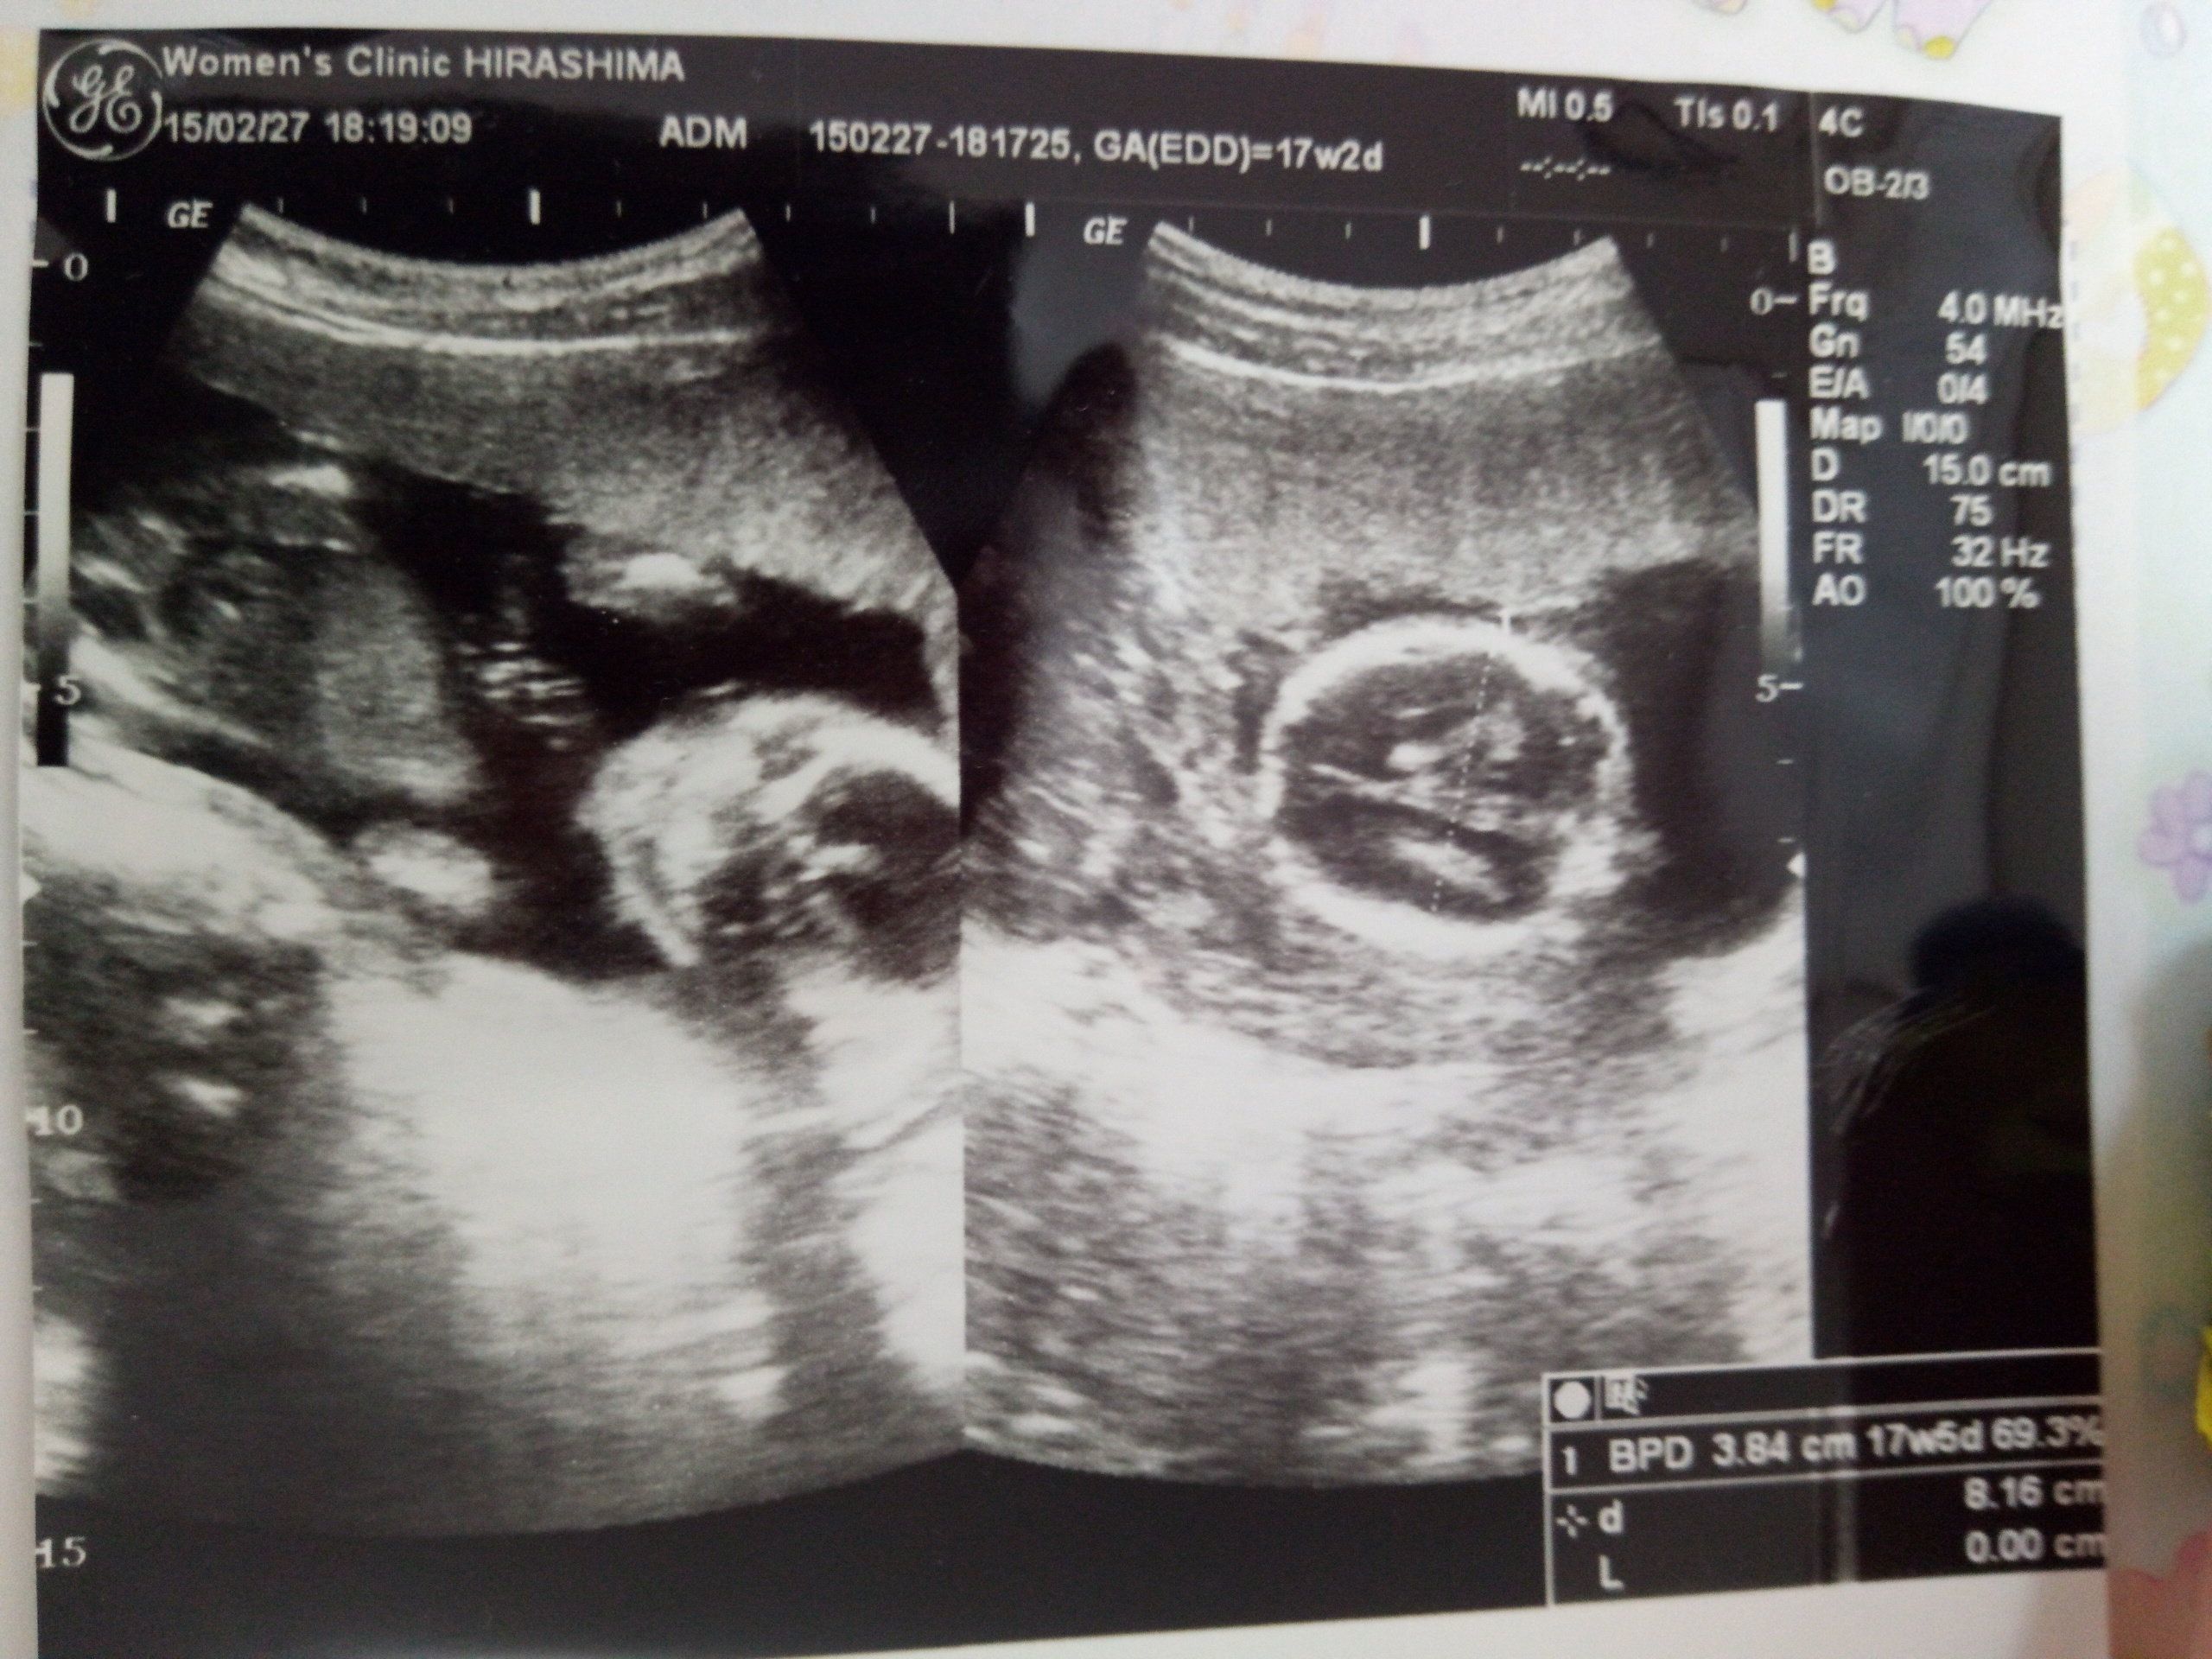

妊娠17週のエコー写真 ずいぶん大きくなった。成長を実感

当時、母乳育児をしたかったため、夜も母子同室でいられる産院を必死で探し、実家から30分程の病院にようやく受け入れてもらうことができました。これは、「べびちゃん」の全身が一枚に収まっていた最後の一枚です。